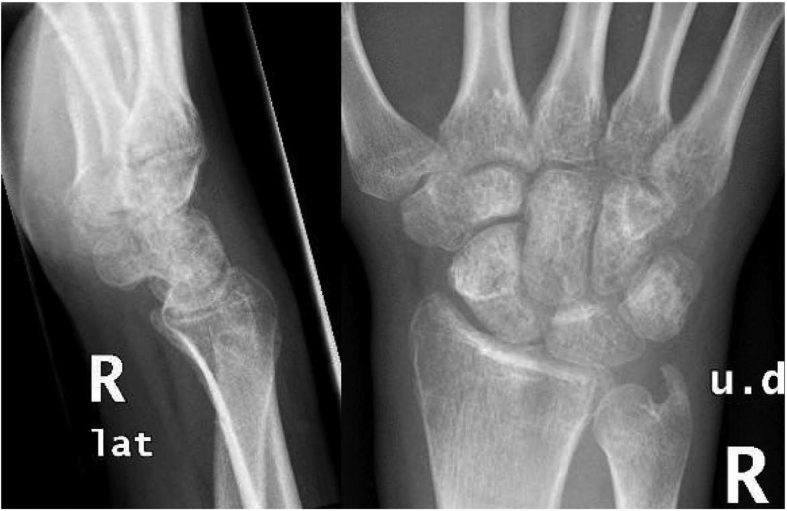

两周后,对伤口进行检查,发现克氏针部位干燥干净。手术后八周,取出克氏针,使用可拆卸夹板,开始职业治疗(图4)。一个月后,患者注意到明显改善。视觉模拟量表(VAS)评分为0,Q-DASH评分为22.7。握力为15公斤,而另一侧为42公斤。X射线显示DRUJ符合要求。术后六个月,患者对自己的手腕运动感到满意,参加了所有日常活动。患者的屈/伸弧度已提高到60/50°,旋后弧度提高到75/40,Q-DASH评分为18。在一年的随访中,运动范围没有改变,最后一次Q-DASH得分是9(图5)。

图4. 克氏针取出后手腕的X线照片。